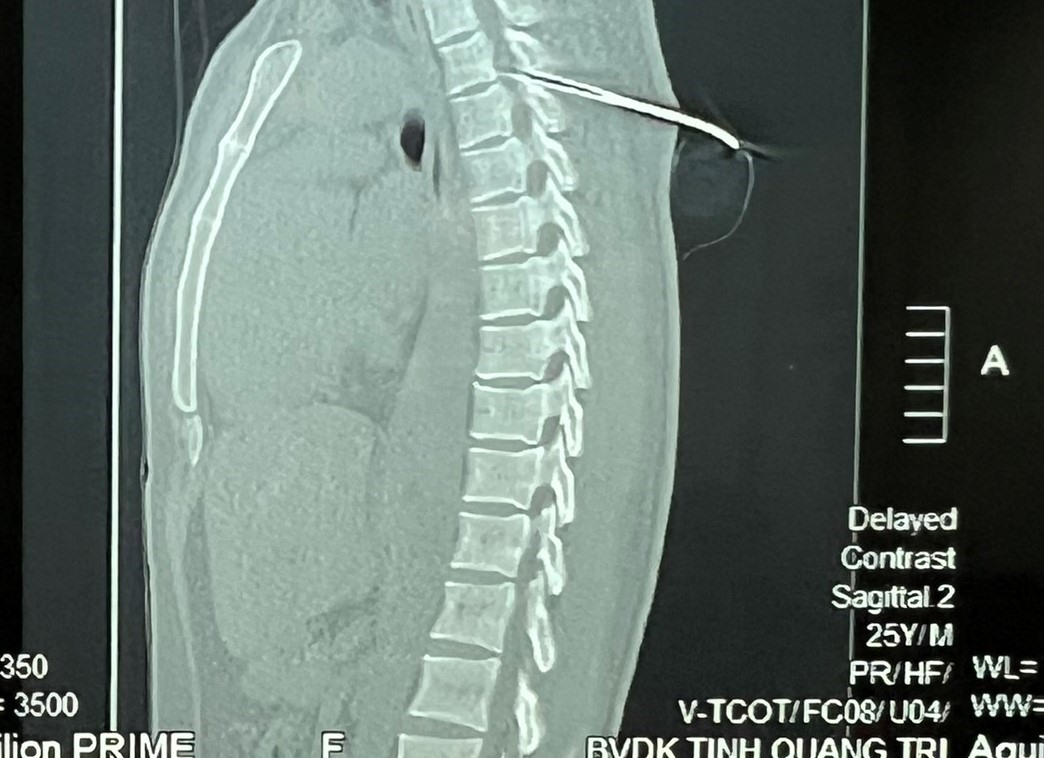

Trước đó, vào tối 31.3, V. được xe cấp cứu chuyển từ Trung tâm Y tế huyện Đakrông về Bệnh viện Đa khoa tỉnh Quảng Trị - trong tình trạng bị 1 mũi tên bắn cá bằng sắt xuyên vào người từ phía sau.

Sau khi xác định vị trí mũi tên, bệnh nhân V. được chuyển mổ cấp cứu.

Các y bác sĩ của Khoa Ngoại chấn thương bỏng Bệnh viện Đa khoa tỉnh Quảng Trị đã cắt xương đốt sống, mở ống sống để lấy mũi tên ra, sau đó vá lại.